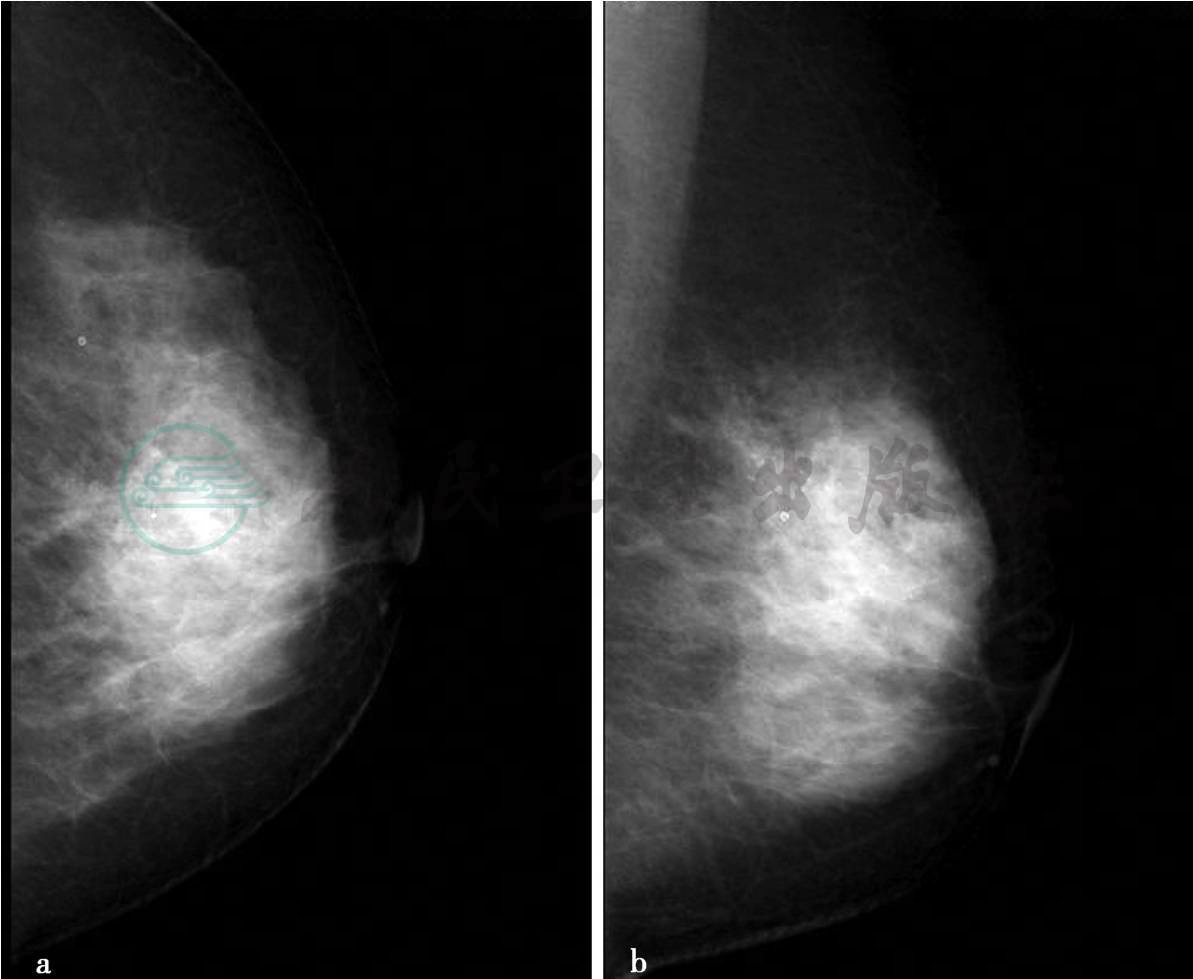

(1)病例2:

X线及超声检查。

图1 图1a,左乳X线头尾位。图1b,左乳X线内外斜位。图1c,左乳钙化区局部放大片。图1d,切除标本钙化区局部放大片。X线显示双乳呈致密型乳腺,左乳中上可见多发不定型及模糊的细小钙化,呈多发成簇的区域性分布,该钙化于放大片显示明显(图c),局部腺体结构不良,未见明确肿块。图1e,左乳病变二维超声图。超声显示左乳中上方腺体局限增厚,厚度约2.3cm,内部回声致密、增强、不均匀,其内可见约0.8cm×0.6cm不规则低回声反射区,边界不清,内部回声不均匀,其中可见多发点状强回声钙化